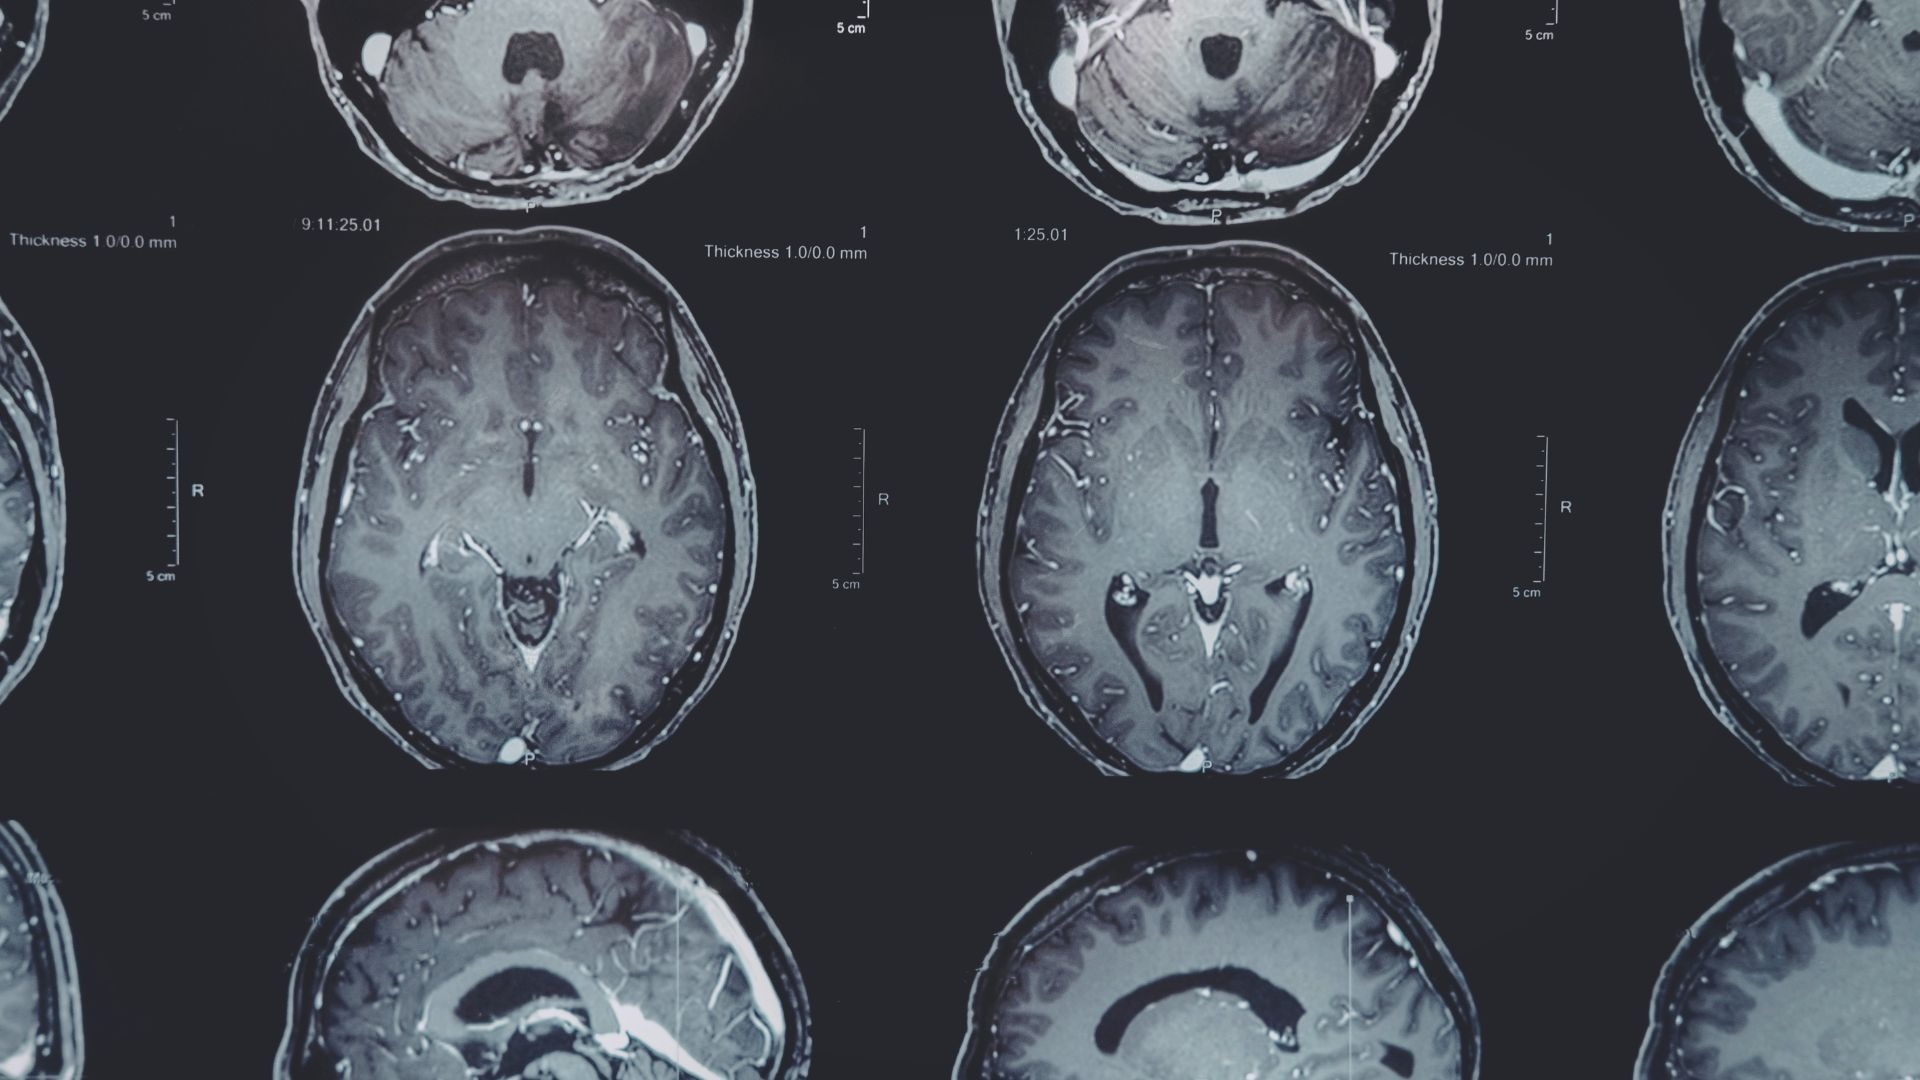

Neurobiologicznie o stresie

Mózg, dieta i techniki regulacji

Jak przewlekły stres wpływa na Twoje ciało, mózg i jelita